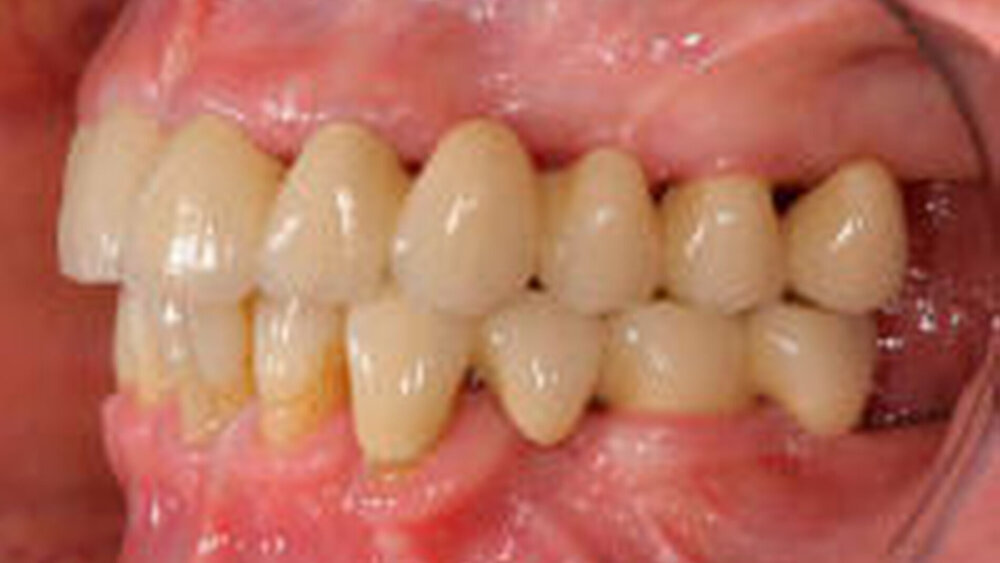

Bei dem von Käyser formulierten und dessen Arbeitsgruppe seit vielen Jahren intensiv wissenschaftlich bearbeiteten Konzept der verkürzten Zahnreihe handelt es sich um einen gut dokumentierten Therapieansatz in der zahnärztlichen Prothetik [Fontijn- Tekamp et al., 2000; Käyser et al., 1982; Sarita et al., 2003a; Sarita et al., 2003c; Witter et al., 1989; Witter et al., 1991; Witter et al., 1994a; Witter et al., 1994b; Witter et al., 1995]. Kurzgefasst lässt sich das Konzept derart zusammenfassen, dass Zähne nur dann ersetzt werden sollten, wenn sie erforderlich sind, um die essenziellen Funktionen wie Ästhetik, funktionellen Komfort und okklusale Stabilität wieder herzustellen. Die Konzeption folgt der Erkenntnis, dass die Bedeutung fehlender Molarenabstützung für die Entstehung von CMD überschätzt und die Fähigkeit des Körpers, nach Zahnverlust mit der Bildung eines neuen stabilen Gleichgewichtszustandes (Kompensation) zu reagieren, unterschätzt wurde [Allen et al., 1995; Sarita et al., 2003b; Sarita et al., 2003c; Witter et al., 1994a; Witter et al., 1994b; Witter et al., 1997; Witter et al., 1999; Witter et al., 2002]. Dem Konzept der verkürzten Zahnreihe liegt die Einteilung in drei unterschiedliche funktionelle Niveaus zu Grunde, die für einander überlappende Altersbereiche minimal erforderliche Zahnzahlen bei günstiger Verteilung definieren (Abbildung 1). Dabei wird der ausschließliche Verlust des zweiten Molaren nicht berücksichtigt. Die Festlegung der Zahnzahl basiert auf einer günstigen Verteilung mit möglichst gleichmäßiger okklusaler Abstützung der Zähne (Abbildung 1). Während das optimale Niveau 1 dem jüngeren und mittleren Erwachsenenalter (20 bis 50 Jahre) zugeordnet wird, wird das suboptimale Niveau 2 für Patienten des mittleren und höheren Alters (40 bis 80 Jahre) als geeignet angesehen, das minimale funktionelle Niveau für Patienten höheren Alters ( 70 Jahre).

Niveau 1:Optimales Niveau mit 24 Zähnen, zum Beispiel beim Vorhandensein aller Frontzähne, Prämolaren und der ersten Molaren.

Niveau 2.:Suboptimales Niveau mit 20 günstig verteilten Zähnen. Eine solche Situation kann zum Beispiel bei Vorhandensein aller Frontzähne und Prämolaren auftreten.

Niveau 3.:Minimales Funktionsniveau mit 16 günstig verteilten Zähnen, zum Beispiel bei Vorhandensein aller Frontzähne und ersten Prämolaren.